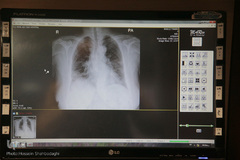

بیمارستان سپاه علی ابن ابیطالب (ع) قم روزگاری میزبان مجروح‌های جنگ تحمیلی و بمباران‌های رژیم بعث عراق بود و حالا با شیوع بیماری کرونا در قم به عنوان سومین بیمارستان برای درمان و پذیرش افرادی است که به این بیماری دچار شده‌اند. آنچه خدمت به خلق خداست و عاشقانه در این مجال رخ می‌دهد.